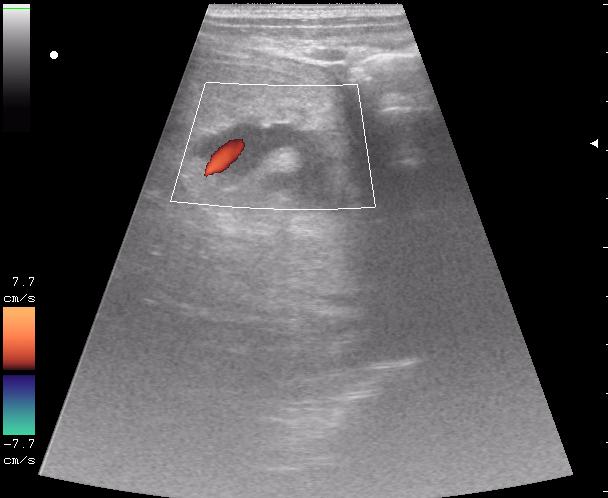

По поводу "разможжения" ткани паренхиматозного органа при травме. Скорее всего-это участки попитывания кровью,т.н. имбибиция.